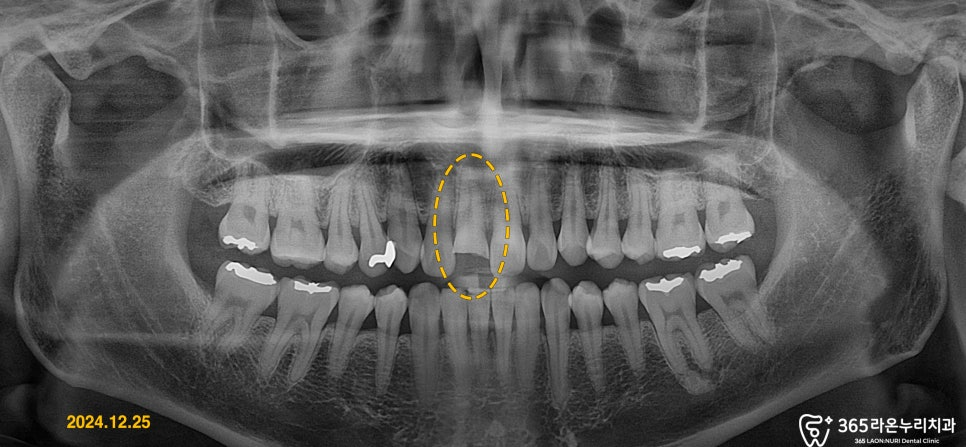

우선 엑스레이 촬영을 통해

정확하게 치아의 상태를

파악할 필요가 있습니다.

엑스레이와 앞니의 상태를

종합적으로 판단했을 때,

치수가 드러난 증상은 딱히

없어 보였습니다.

오산 신장동 치과 에서는

치수가 아직 살아 있는 것을

확인하고 신경 치료 없이

자연 치아로 최대한 살려내기로

결심하게 되었습니다.